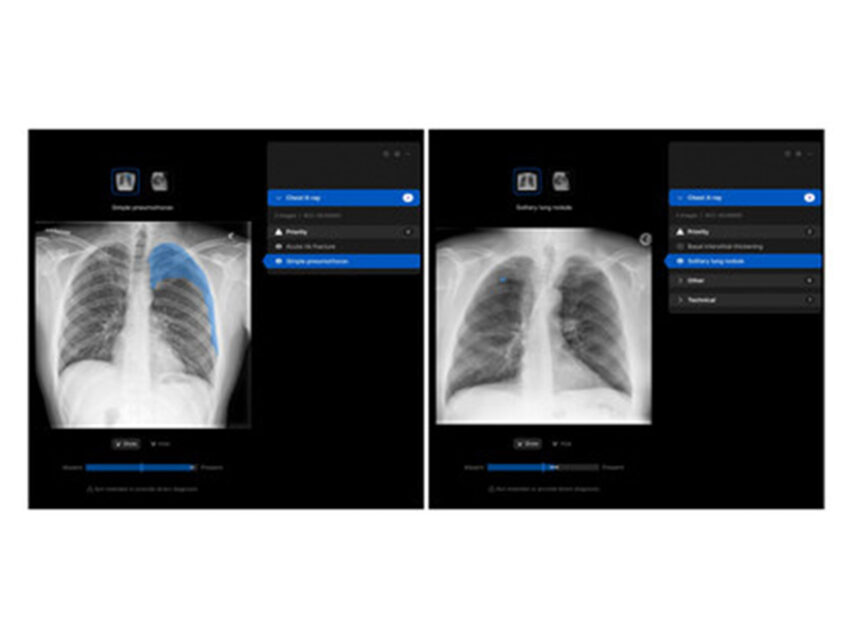

The solution is deployed within the radiology department, where it will assist radiologists by triaging studies, identifying and localising findings, and generating AI-assisted draft reports. These draft reports are reviewed and validated by radiologists prior to sign-off, ensuring full clinical oversight and control.

Harrison.ai CXR is approved by the Central Drugs Standard Control Organization (CDSCO) in India and is CE certified. It is designed to support clinicians across a wide range of chest X-ray findings. The solution acts as a clinical decision-support tool, assisting radiologists without replacing clinical judgment.

“We are proud to partner with Manipal Hospitals on the deployment of Harrison’s CXR solution in India,” said Dr Aengus Tran, CEO of Harrison.ai. “The solution which can detect and localise close to 125 findings helps clinicians ensure accuracy of diagnosis. This collaboration reflects a shared vision to responsibly apply AI in healthcare, supporting clinicians, improving efficiency, and ultimately enhancing patient care and experience.”